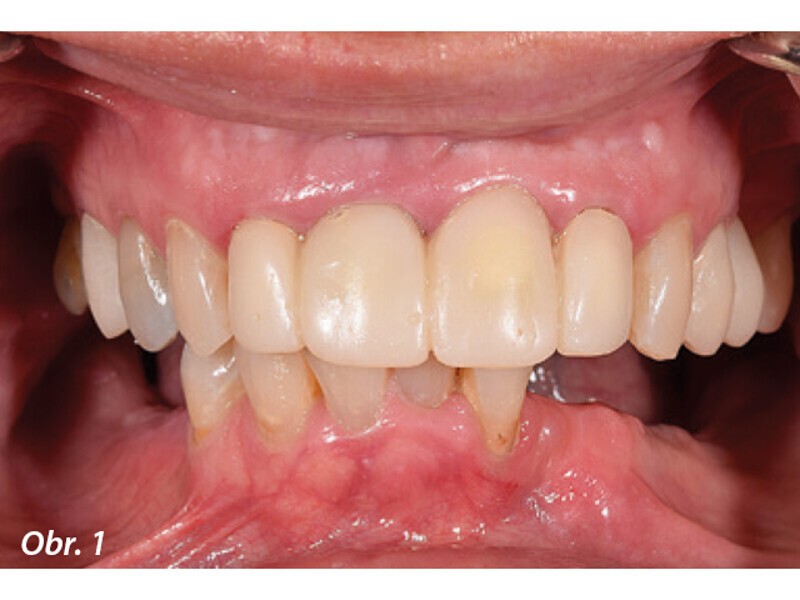

Rekonstrukce chrupu v dolní čelisti